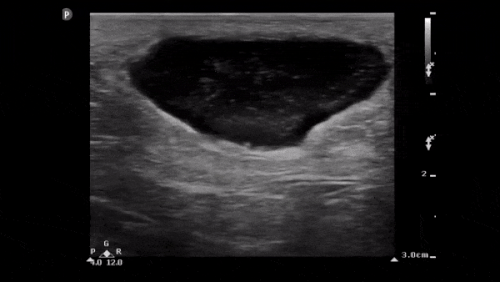

You decide to investigate it with an ultrasound scan showing the following:

• US of the swelling demonstrates heteroechoic shadows in the pectoralis major muscle above the rib and pleura which can be seen deep to this, with pockets of hypoechoic fluid and a hyperechoic shadow. This is consistent with an abscess.

The ultrasound also shows oedema of the periosteum of the 1st rib, seen as the irregularity of the cortex. This is a periosteal reaction, a nonspecific radiological finding indicating periosteal irritation[1] that can be seen in osteal malignancy, infection or trauma, amongst other things.

• Given the history and background, this is most likely a ‘cold abscess’ in the context of Mycobacterium tuberculosis infection.

The departmental ultrasound report noted: “The left pectoralis major intramuscular collection demonstrated heterogeneous echotexture with mostly solid looking components and scattered anechoic cystic regions.”